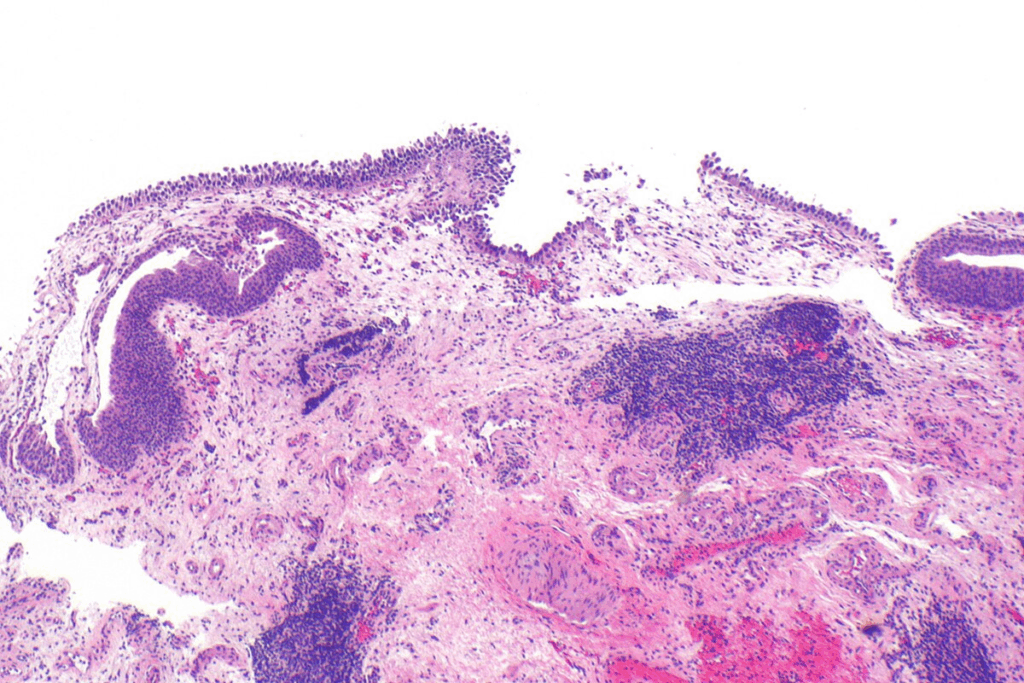

Carcinoma in situ is a key stage in cancer growth. It’s important to understand its cell and microscopic details. To explain in situ cancer, we need to know what makes it different from normal cells and invasive cancer.

Cellular Characteristics of Carcinoma In Situ

Carcinoma in situ cells show odd traits that set them apart from normal cells. These traits include:

Even with these oddities, CIS cells haven’t broken through the basement membrane. This membrane is key in keeping epithelial cells separate from the tissue below.

Diagnosing carcinoma in situ involves looking at it under a microscope. CIS cells are recognized by their unique features, such as:

Pathologists use these signs to spot carcinoma in situ. They can tell it apart from benign conditions and invasive cancer.